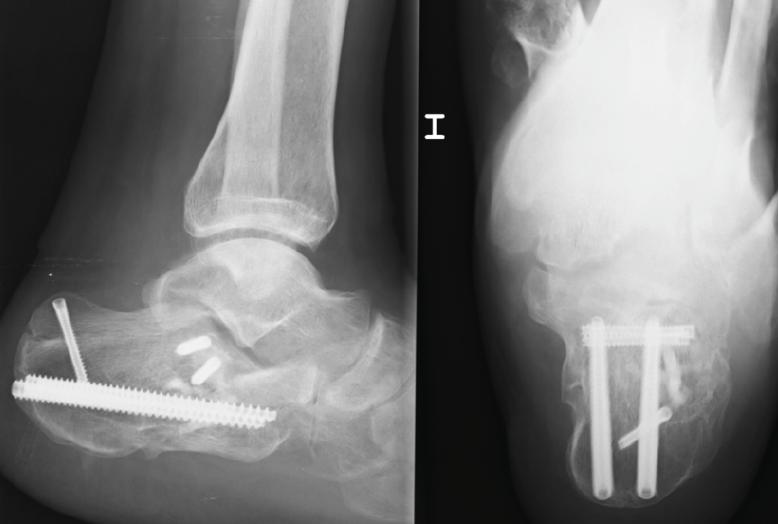

Cuando tenemos todos los fragmentos en su posición anatómica, habiéndose conseguido la reducción de la superficie subastragalina posterior, se fijan de manera provisional dichos fragmentos con agujas de Kirschner (aK) de 1,0 o 1,2. Estas aK fijan los fragmentos laterales de la fractura a la zona medial que normalmente está intacta. Se comprueba bajo fluoroscopio (proyección lateral) que se ha restablecido el ángulo de Böhler (Figura 3) y se fija de forma definitiva con 2 o 3 tornillos canulados de lateral a medial.

Figura 5. Varón de 37 años con fractura del calcáneo de Sanders de tipo IIB tras caída de altura. En la imagen de la tomografía computarizada se observa hundimiento de la zona lateral de la subastragalina posterior y un trazo posterior “en lengua”. Ángulo de Böhler precirugía de 8,5°.

A la hora de corregir el varo-valgo y la longitud del calcáneo colocamos un pin Steinmann o aK de 3,0 o 4,0 en la tuberosidad posterior y damos angulación varo o valgo (Figura 4) según necesite cada caso y siempre comprobando con la fluoroscopia (proyección axial). Una vez conseguida la angulación correcta, se fija de forma definitiva con 2 tornillos canulados de posterior a anterior (Figuras 5 y 6).

Figura 6. Se fijó con 2 tornillos canulados de lateral a medial, 2 tornillos de posterior a anterior y 1 tornillo cerrando el trazo en lengua. Ángulo de Böhler poscirugía de 30,9° y a los 3 meses de 32°. No presentó ninguna complicación.